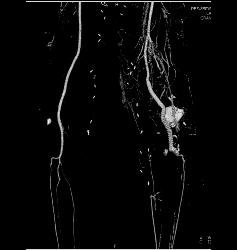

Superior Mesenteric Artery (SMA) Occlusion